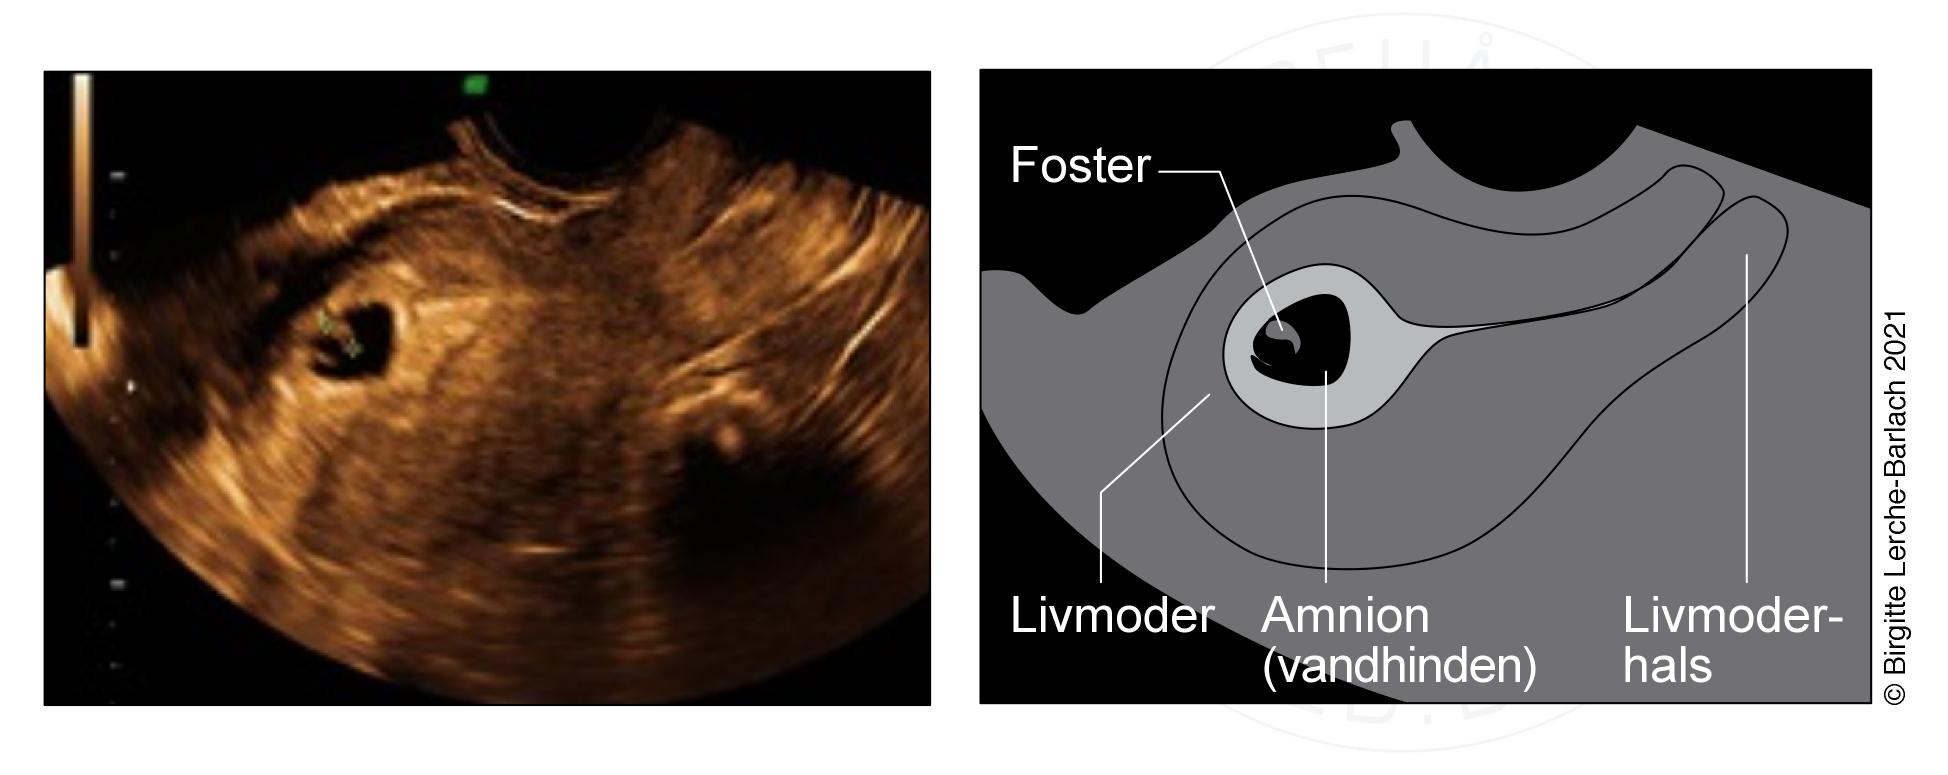

Billede ovenfor:

Ultralydsskanningen viser en meget tidlig graviditet i livmoderen (intrauterin graviditet). Fosteret er omgivet af fostervand (amnion).